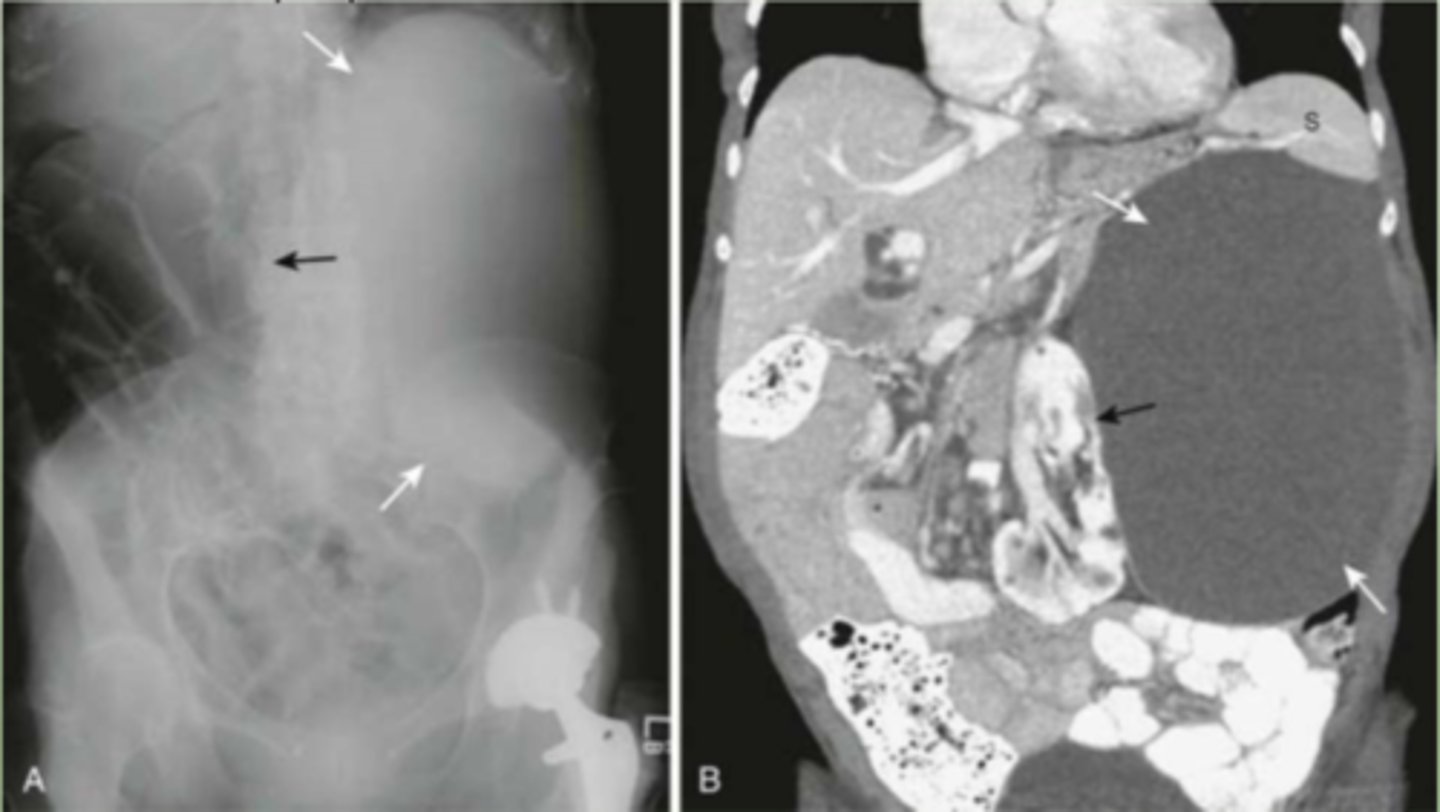

splenomegaly

enlarged spleen, projects well below 12th posterior rib

spleen

most highly vascular organ, most injured organ in blunt trauma

CT is diagnostic study of choice

splenic laceration

hemorrhage and hematoma present, dark fluid is blood surrounding spleen